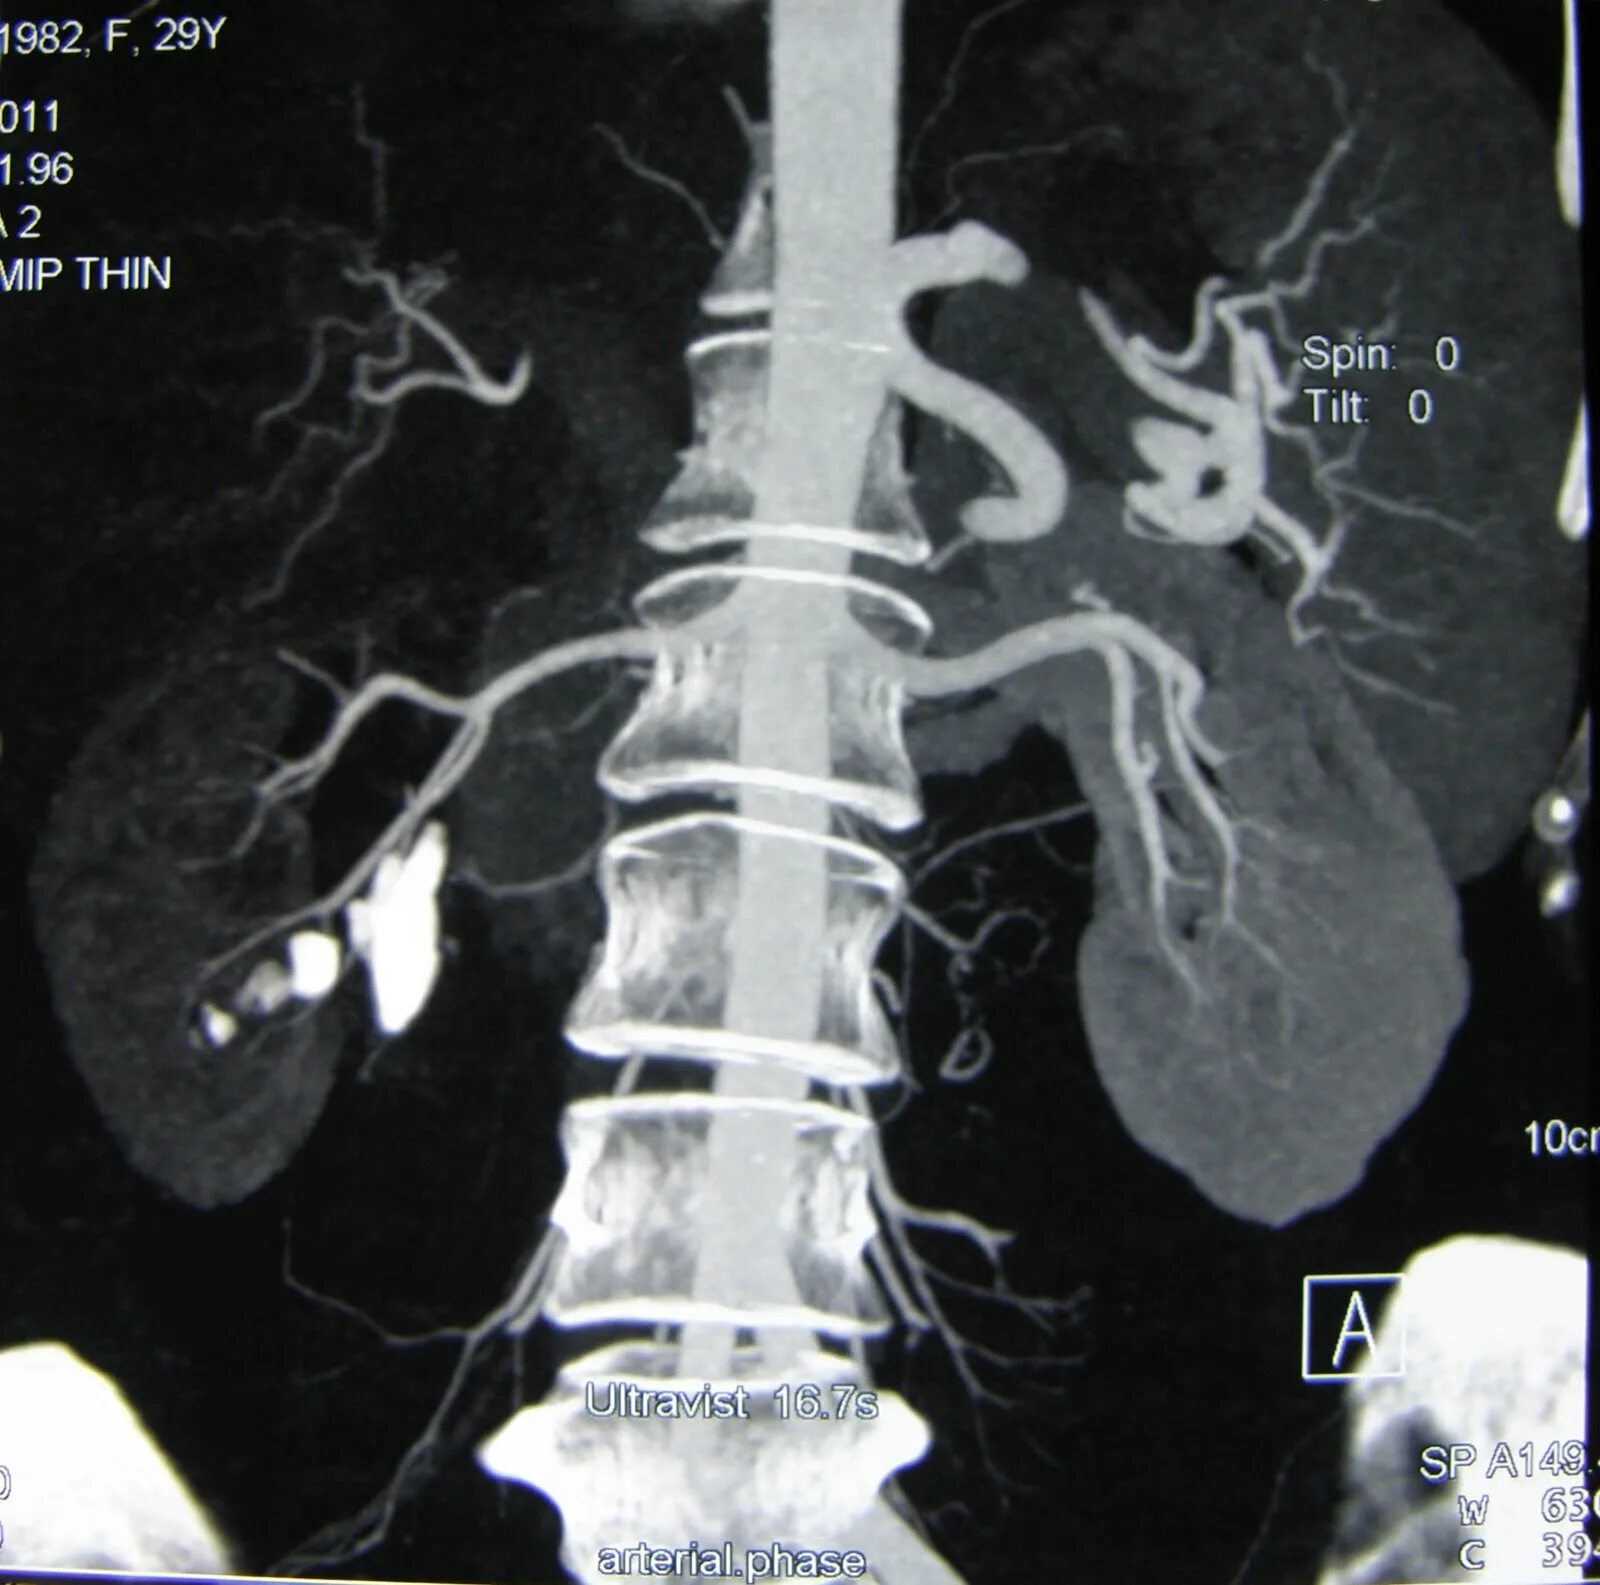

Кт почек с контрастированием как проводится